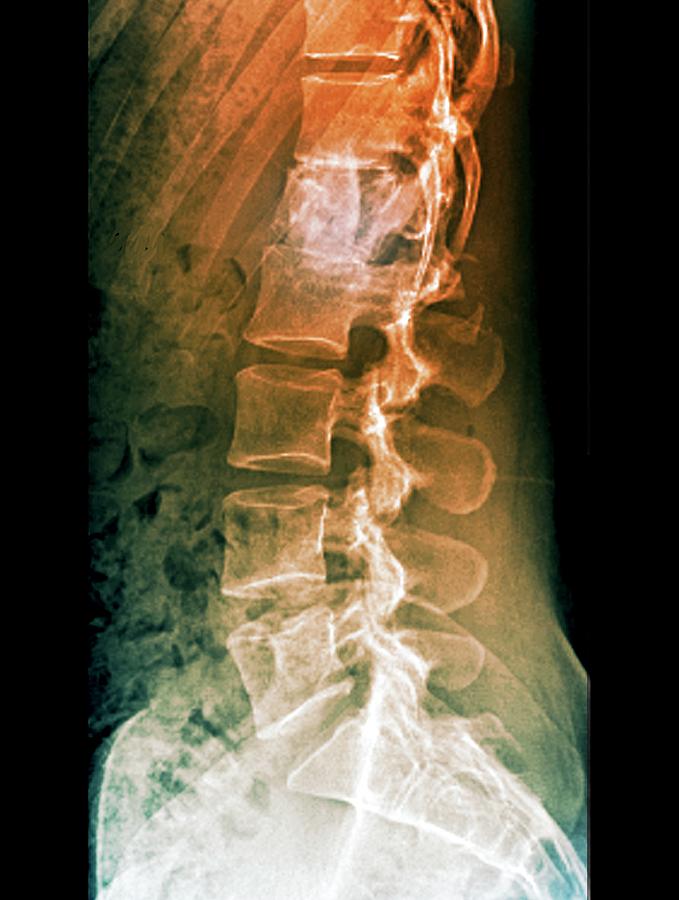

From www.sciencephoto.com

Fixed spinal fracture, Xray Stock Image C025/2512 Science Photo Library Can A Spinal Fracture Be Fixed Without proper care, a spinal fracture that. A minor fracture may heal. Treatment and recovery for a spinal fracture depend on the severity and location. spinal fractures can be extremely painful and debilitating, so it is important to get medical help promptly if you think you have fractured your. spinal fractures involving vertebrae in the lumbar spine (lower. Can A Spinal Fracture Be Fixed.